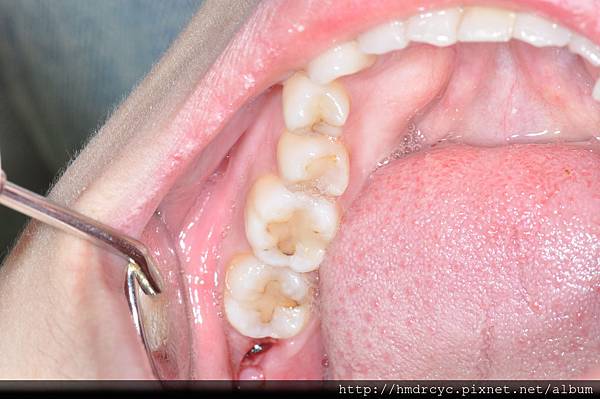

旁邊的牙齒還是要刷乾淨

避免怕碰到傷口不敢刷

結果旁邊牙齒的牙垢累積

第三天就牙肉發炎痛起來了